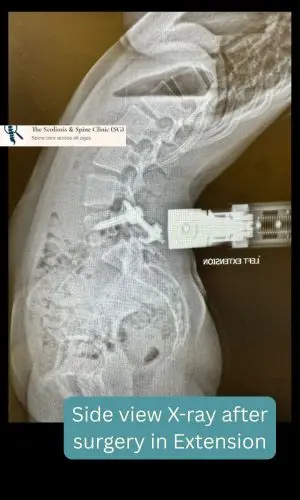

Despite three months of non-operative management, her ache persisted. A decision was made to proceed with surgical repair- a non-fusion motion preserved technique – using direct pars fixation—a targeted approach to stabilize the fracture and restore spinal integrity while maintaining the flexibility.

Side view radiograph in extension of the lower back shows preserved lumbar motions.